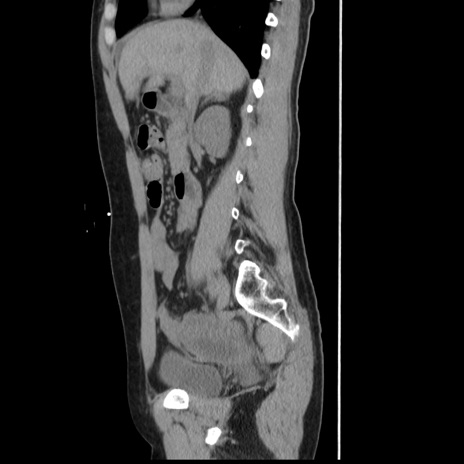

症例10(矢状断像)

【症例】 50歳代女性

【主訴】 腹痛

【現病歴】前日生レバーを食べた。今朝に排便あり。 昼前に突然発症の腹痛を生じ、当院救急外来を受診した。

【既往歴】 子宮筋腫にてで子宮全摘後

【身体所見】 意識清明、腹部:平坦、軟、下腹部やや左を中心に圧痛・反跳痛あり、筋性防御あり

【データ】WBC 7800、CRP 0.07